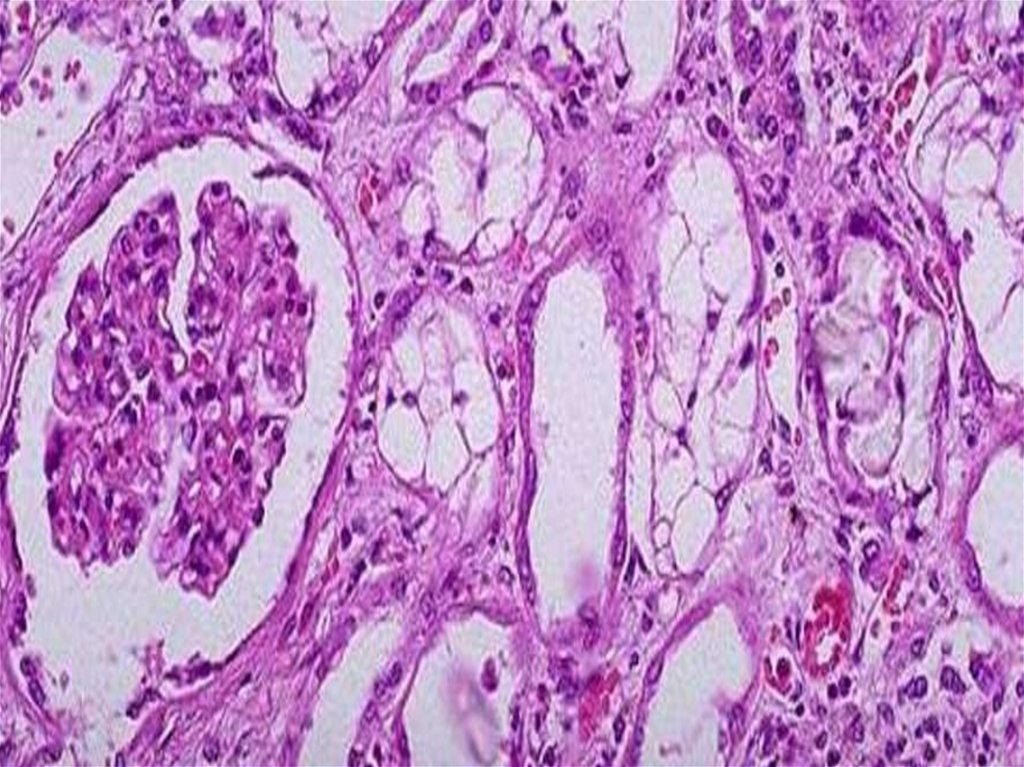

Гидропическая (водяночная):

Характеризуется

появлением в клетке

вакуолей, наполненных

цитоплазматической

жидкостью.

клетки увеличены в объеме,

ядро смещается на

периферию.

Прогрессирование этих

изменений приводит к

распаду ультраструктур

клетки и переполнению

клетки водой. Клетка

превращается в

заполненные жидкостью

баллоны (баллонная

дистрофия).

ПРИЧИНЫ:

1. Гломерулонефрит

2. Сахарный диабет

3. Вирусный и токсический

гепатиты

Исход: неблагоприятный

колликвационный некроз.

Функция органов и тканей

страдает.

Гидропическая дистрофия почки

Гидропическая дистрофия печени